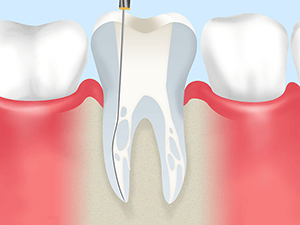

歯内療法(根管治療)とは?

歯内療法とは、重度の虫歯や外傷などによって歯髄(歯の中にある神経)に細菌が感染し病気が発生した場合に行われる歯科治療のことです。

歯内療法とは、重度の虫歯や外傷などによって歯髄(歯の中にある神経)に細菌が感染し病気が発生した場合に行われる歯科治療のことです。

歯内療法の一つである根管治療は、抜歯せず歯を残すために根尖性歯周炎(歯の根の病気)に対して行う治療で、感染源を取り除いて歯の根を綺麗にします。